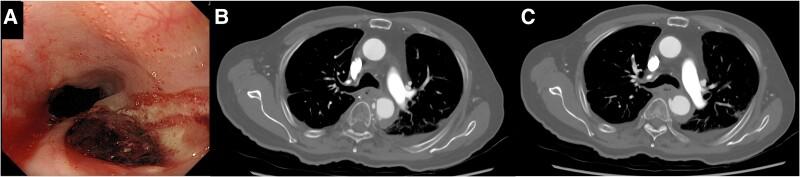

An 84-year-old man was referred to a local hospital with massive haematemesis and transient loss of consciousness. The patient's medical history included radiotherapy for oesophageal cancer 19 years before presentation. Gastrofiberscopy revealed an ulcer in the thoracic oesophagus and no recurrence of oesophageal cancer. Computed tomography (CT) showed that the same area was adjacent to the thoracic aorta and that there was no thoracic aortic aneurysm. The patient was then transferred to our institution for surgical treatment. We diagnosed the patient with an AEF caused by radiotherapy of the oesophagus. Therefore, TEVAR was performed. Due to the patient's advanced age, condition, and the possibility of strong adhesions, there was a high risk that they would be unable to tolerate oesophagectomy to prevent stent graft infection. Therefore, antibiotic therapy was initiated. However, CT revealed a stent graft infection 24 days after TEVAR. The patient died of sepsis 27 days after the procedure.

一名84岁男性因大量呕血和短暂意识丧失被转诊至当地医院。患者的病史包括在就诊前19年接受过食管癌放疗。胃镜检查发现胸段食管有溃疡,且食管癌无复发。计算机断层扫描(CT)显示同一区域与胸主动脉相邻,且无胸主动脉瘤。随后患者被转至我院接受手术治疗。我们诊断该患者为食管放疗引起的AEF。因此,实施了TEVAR。由于患者年龄较大、病情以及存在强力粘连的可能性,他们极有可能无法耐受食管切除术以预防支架移植物感染。因此,开始使用抗生素治疗。然而,CT显示TEVAR术后24天出现支架移植物感染。患者在手术后27天死于败血症。